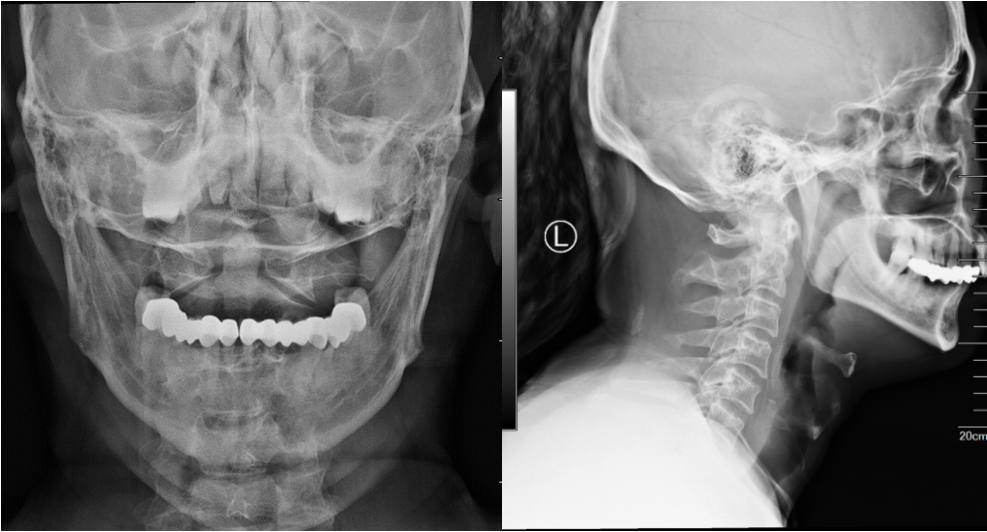

患者颈椎术后复查,置钉精准,内固定可靠

经过医护人员的精心治疗和护理,患者术后恢复良好。术后第二天,患者已佩戴颈托下床活动。家属对姜主任和医护人员的精湛医术和热心服务表示衷心的感谢。这次千里之行,完全值得!